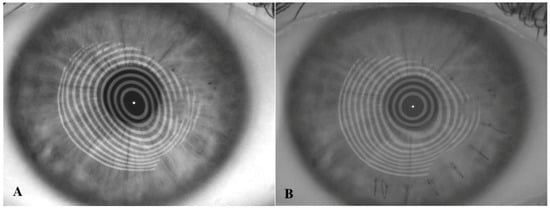

2.1. Topography